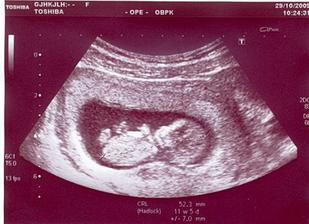

*29.10.2009 ... NT ultrazvuk (NT 1,3)